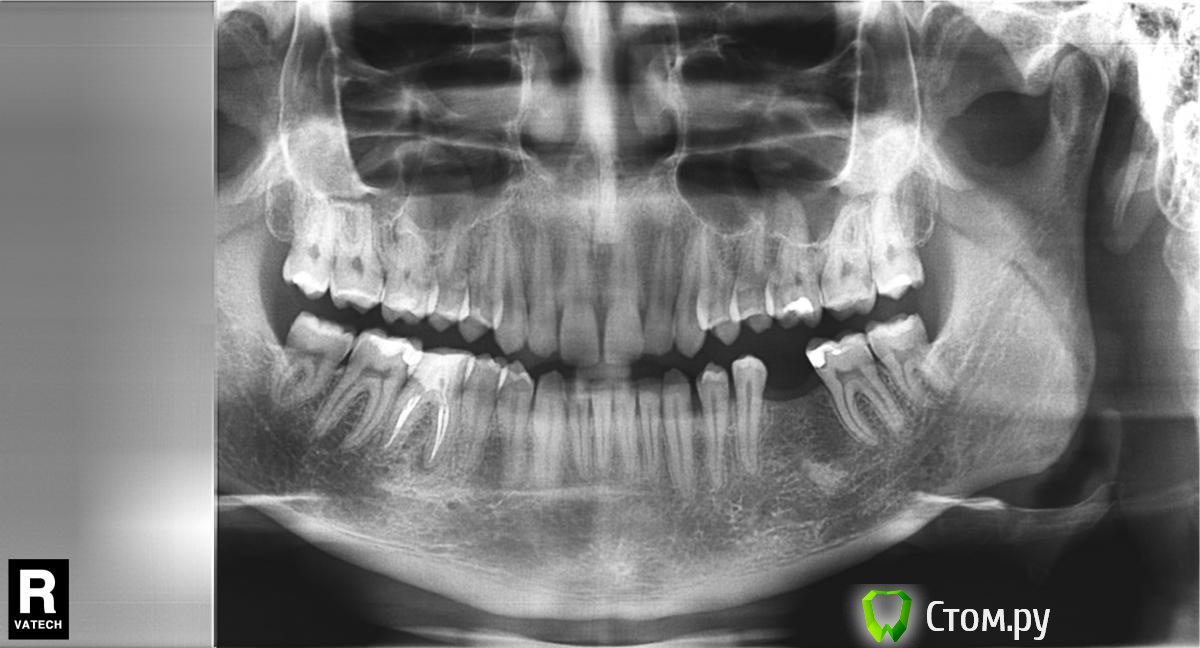

bobrdobr Опубликовано 5 февраля, 2014 Автор Поделиться Опубликовано 5 февраля, 2014 Огромное спасибо всем докторам, кто отписывается в теме. Сегодня история получила неожиданное продолжение. Побывал на очном приеме Хирурга 3. Cтавит Xive и Bicon. К моему удивлению, он однозначно предложил мне Bicon. Аргументы за Bicon такие (пишу по памяти, возможны неточности!):За время отсутствия зуба кость ушла на 1-2 мм. Винтовой имплант (в т.ч. Xive) в моей ситуации требует укрепления костной стенки остеопластическим материалом с мембраной. Без костной пластики поставить можно, но стенка будет тонкой и воспаление под десной - дело времениBicon позволяет обойтись без костной пластики в моем случаеУ Bicon коронка и абатмент соединяются цементом в руках, а не во рту, подтекание цемента исключеноУ Bicon герметичное внутреннее конусное соединениеУ Bicon абатмент имеет выраженную шейку и ее можно дофрезеровать, учитывая размеры основания коронки и особенности десны. У винтовых имплантов абатмент внутри, а на жевательном зубе винт всегда уже чем коронка, поэтому соединение коронка-имплант получается менее анатомичным.При необходимости можно вынимать абатмент с коронкой и ставить обратноБыли озвучены такие "минусы" BiconНе подходят для передних зубов и клыков, вываливаются из-за наличия "боковой" нагрузки. Но у меня 46, так что будто бы все в порядке.Дают небольшую усадку, поэтому коронка ставится выше на пару мм. Жевать в первое время может быть не очень удобноОтзывы о Bicon на форуме не радуют. К моему удивлению, ортопед, работающий в паре с Хирургом 3, положительно отнесся к Bicon. Говорит, что ему протезировать на Bicon даже удобнее, чем на Xive. Хирург 2 также имеет в арсенале Bicon, но мне на консультации предложил винтовой Semados. Посчитал ненужной пластику? Основная его претензия к Bicon: сложность точного позиционирования из-за установки "заколачиванием". Буду рад услышать ваши ценные указания . Прикладываю свежий панорамный снимок. А еще лучше найдите ортопеда и идите к тому хирургу, которого он посоветует. Хорошая идея, спасибо! Еще как минимум к одному хирургу хочу попасть, чтобы прояснить вопрос с костной пластикой. Ссылка на комментарий

bobrdobr Опубликовано 17 февраля, 2014 Автор Поделиться Опубликовано 17 февраля, 2014 Добрый всем день. Сделал КТ. Снимок выложил на Яндекс.Дискhttp://yadi.sk/d/-CHDNu-nJ45Wy Посмотрите пожалуйста. Вопрос прежний: нужна ли костная пластика в каком-то виде перед установкой винтового импланта? Ссылка на комментарий

bobrdobr Опубликовано 17 февраля, 2014 Автор Поделиться Опубликовано 17 февраля, 2014 Хорошо. Так подойдет? Ссылка на комментарий

Bier Опубликовано 17 февраля, 2014 Поделиться Опубликовано 17 февраля, 2014 судя по фото, скорее всего нужна. От КТ нужен срез горизонтальной плоскости - вид сверху на костный гребень, на 1 мм ниже его вершины. Ссылка на комментарий

bobrdobr Опубликовано 18 февраля, 2014 Автор Поделиться Опубликовано 18 февраля, 2014 (изменено) Имплант был предложен Semados 4,1*11,5 без костной пластики. судя по фото, скорее всего нужна. От КТ нужен срез горизонтальной плоскости - вид сверху на костный гребень, на 1 мм ниже его вершины. Сейчас попробую. Прикладываю 4 снимка: на уровне гребня (как мне кажется) и на 1,2,3 и мм. ниже. Изменено 18 февраля, 2014 пользователем bobrdobr Ссылка на комментарий